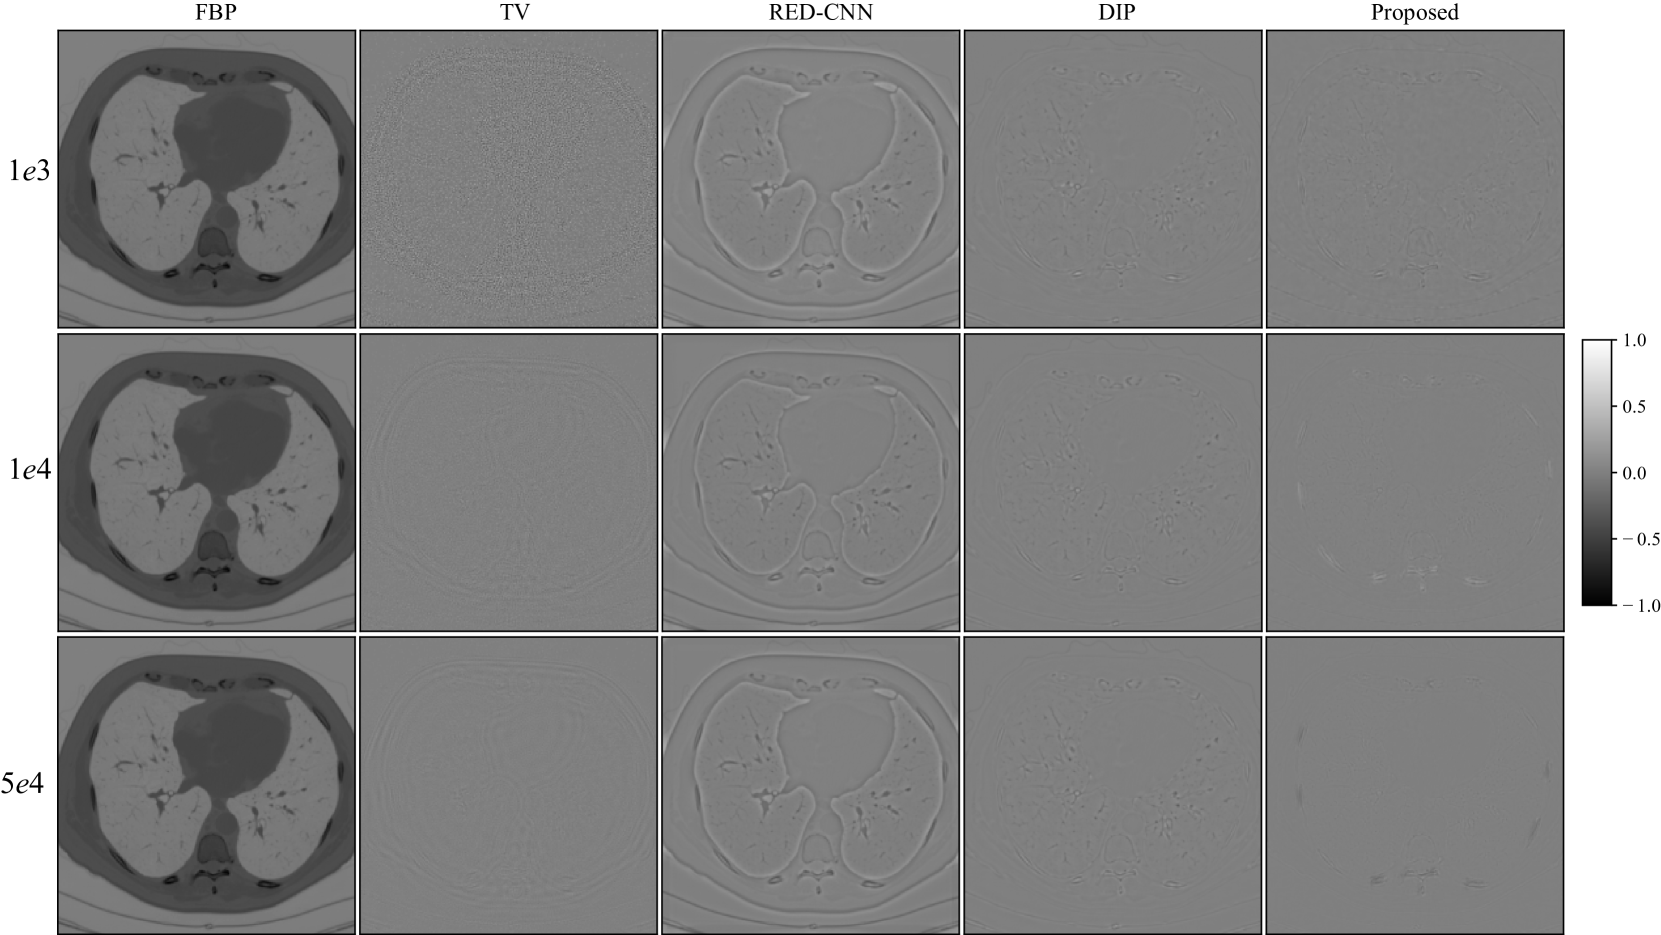

Refer to caption

Figure 6: Reconstruction errors of LoDoPab-CT data at different dose levels by different methods.

LoDoPab-CT data: For the LoDoPab-CT data, the reconstruction results are shown in Fig. 5. From Fig. 5, we can observe that the performance of each reconstruction method is similar to their performance for the above AAPM challenge data reconstruction. The reconstructed results by FBP and TV suffer from noise and artifacts, although TV can suppress a lot of noise. The textures and edges in the reconstructed results by RED-CNN are smoothed out, whereas DIP can remove noise and preserve tiny structures more effectively. The proposed method achieves the best performance with regard to noise suppression and preservation of tiny structures. Furthermore, the reconstruction errors (Fig. 6) further demonstrate that FBP method sacrifices a lot of useful information. TV and RED-CNN can effectively improve the reconstructed results by FPB; however, TV can not preserver edges well, and RED-CNN tends to smooth edges and textures. DIP has slighter residual errors in terms of edges and textures. Compared with the competitive methods, the proposed method significantly decreases the reconstruction errors by FBP and achieves minimal reconstruction errors.